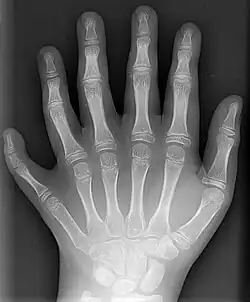

Trazado con Potrace en Inkscape a imagen SVG de ocho colores en 2006 (50 KB) -